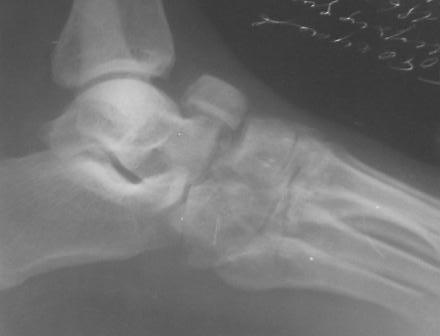

Re: Застарелый вывых ладьевидной кости стопы

По данному случаю, оказалось 3 месяца назад было произведена Р-графия в райбольнице, но больной предпочел лечится у табиба. Присылаю первичные снимки.